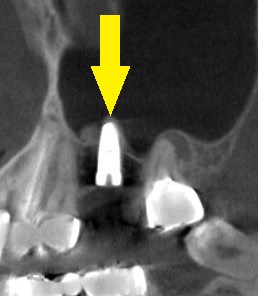

ただ、ある程度の骨量はありましたので、ソケットリフトという、骨造成術を併用してインプラント埋入術を行なうことで同意をいただきました。

下の写真3段目が術後のCT、ソケットリフトによりインプラントが埋入され周囲に骨補填材が白く写っています。